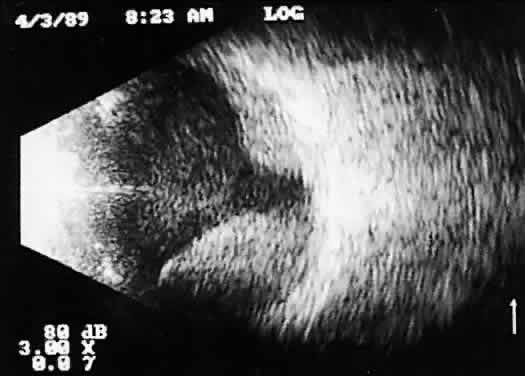

tissue characterization. The B-scan image, a two-dimensional crosssectional display of the globe and orbit, is more easily interpreted than A-scan, especially by examiners familiar with interpretation of ophthalmic pathology, where microscopic and gross crosssectional evaluation of the globe and orbit are routine and often topographically similar to B-scan cross-sections. Several concepts are critical to accurate interpretation of B-scans. These concepts, although relatively easy to define, require considerable experience before the examiner feels comfortable with diagnosis in opaque media situations. These concepts are real time, gray scale, and threedimensional thinking. Real time refers to the display of motion or movement during B-scan imaging. This capability is one of the greatest advantages of B-scan. Differences in mobility of a variety of movable intraocular abnormalities can be easily detected. For example, the rapid movement of vitreous hemorrhage is usually easy to appreciate and differentiate from the slower, undulating movements of a recent, rhegmatogenous retinal detachment. On occasion, movement of intraocular structures can be used for detecting abnormalities that lie immediately behind vitreous opacification and may be seen only when the vitreous opacities are moved away from the ocular wall, set in motion by command voluntary movements of the patient's globe (Fig. 5). Gray scale refers to the variable gray tone of display screen echoes. Strong returning signals (echoes) appear white, whereas weaker reflections are seen as gray, the shade depending on echo strength. Examples of strong reflectors of sound include retinal tissue, sclera, and calcifications of any type (Fig. 6). Weaker echoes from clotted or clumped cells within the vitreous are usually easy to differentiate from the stronger reflectors of sound (Fig. 7). Grading of echo strength may be performed only when the examining ultrasound beam is perpendicular to the object of interest, ensuring the strongest possible reflections. However, in the world of ultrasound interpretation, there are many exception to the rules. Tissues that are usually mild reflectors of sound, such as hemorrhage, can at times appear quite strong, especially in complex or multiple pattern disorders, as frequently occur in severe ocular trauma. These apparent inconsistencies often cause misinterpretation by the novice. With experience obtained by multiple examinations, careful follow-up, and clinical correlation whenever possible, diagnostic acumen rapidly improves.